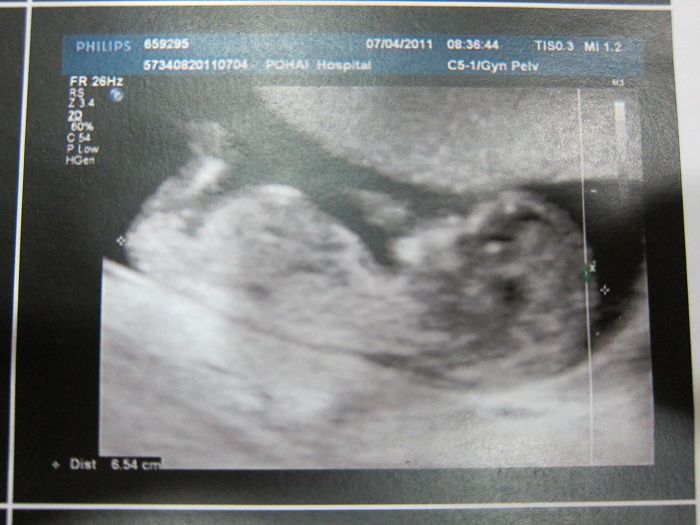

是的!!!我有二寶了!!